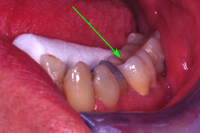

Eine 31 Jahre alte Patientin hatte akute Schmerzen am zweithintersten Backenzahn im Unterkiefer rechts und kam am 26. März 1980 zu uns in die Praxis.

Im Röntgenbild von Abb. 3 ist ein gut erbsengrosses Granulom (Pfeil) an der Wurzelspitze eines toten, devitalen Zahnes feststellbar. Die Patientin wünschte die Erhaltung des Zahnes, zumal auch der vordere Nachbarzahn marktot und beherdet war. Abb. 4 zeigt das Röntgenbild nach der Wurzelfüllung.